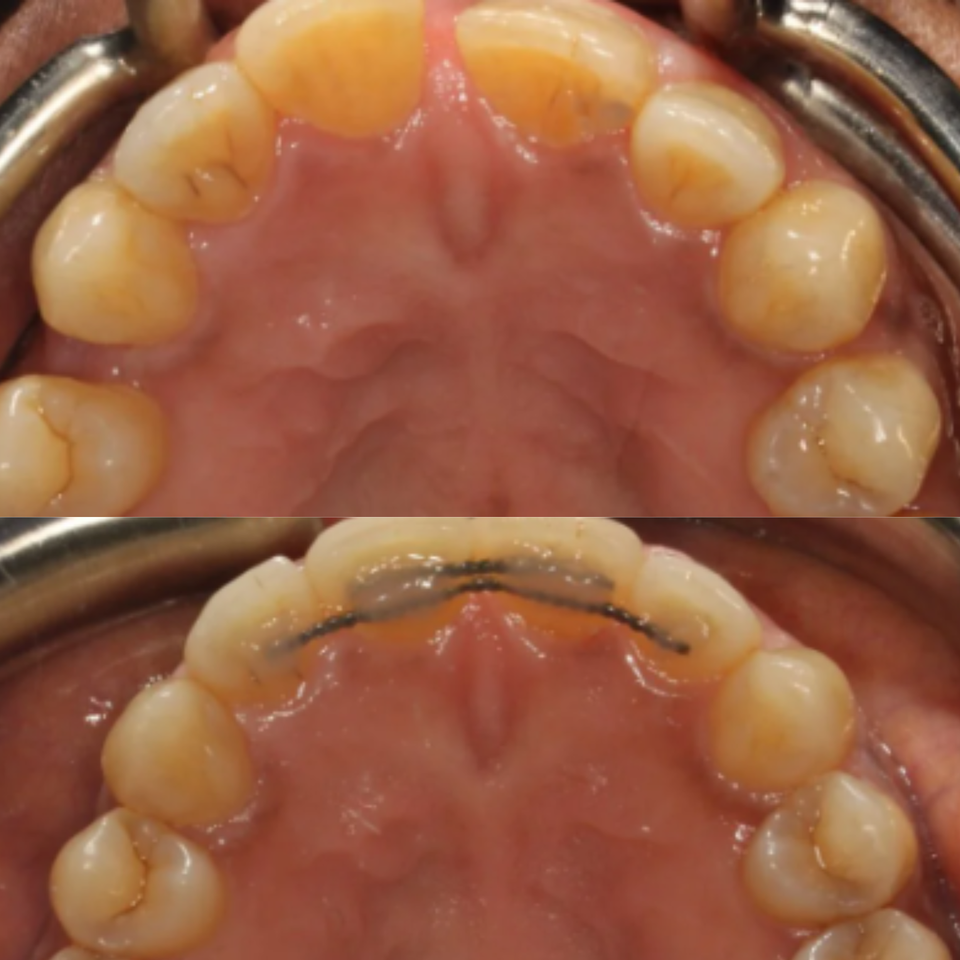

At our practice, we recently helped a patient restore their smile after experiencing a complex dental issue involving a periodontal infection and a root fracture. To fully restore both health and aesthetics, we recommended a comprehensive implant-based solution.

The treatment process included:

• Extraction and Bone Grafting to properly prepare the site for implant placement

• Implant Placement with Soft Tissue Grafting to ensure long-term stability and natural-looking gum contours

• Provisional Implant-Supported Crown to maintain appearance and function during healing

• Final Implant-Supported Crown, custom-designed for strength, beauty, and seamless integration

We are extremely proud of the final result, and most importantly, our patient is now enjoying a healthy, confident smile once again.